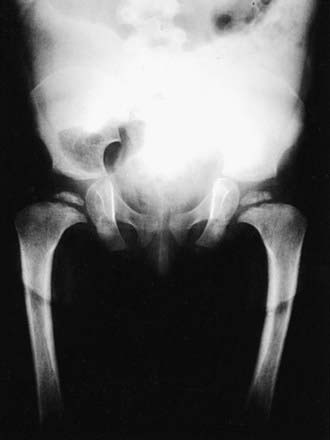

Skeletal radiographs of the newborn reveal short tubular bones, delayed ossification of vertebral bodies, and proximal limb bone epiphyses (Fig. 686-3). Hypoplasia of the odontoid process, a short, square pelvis with a poorly ossified symphysis pubis, and mild irregularity of metaphyses are apparent.

Figure 686-3 Radiograph of spondyloepiphyseal dysplasia congenita pelvis demonstrating squared pelvis, hypoplastic capital femoral epiphyses, and femoral necks that are wide and short.